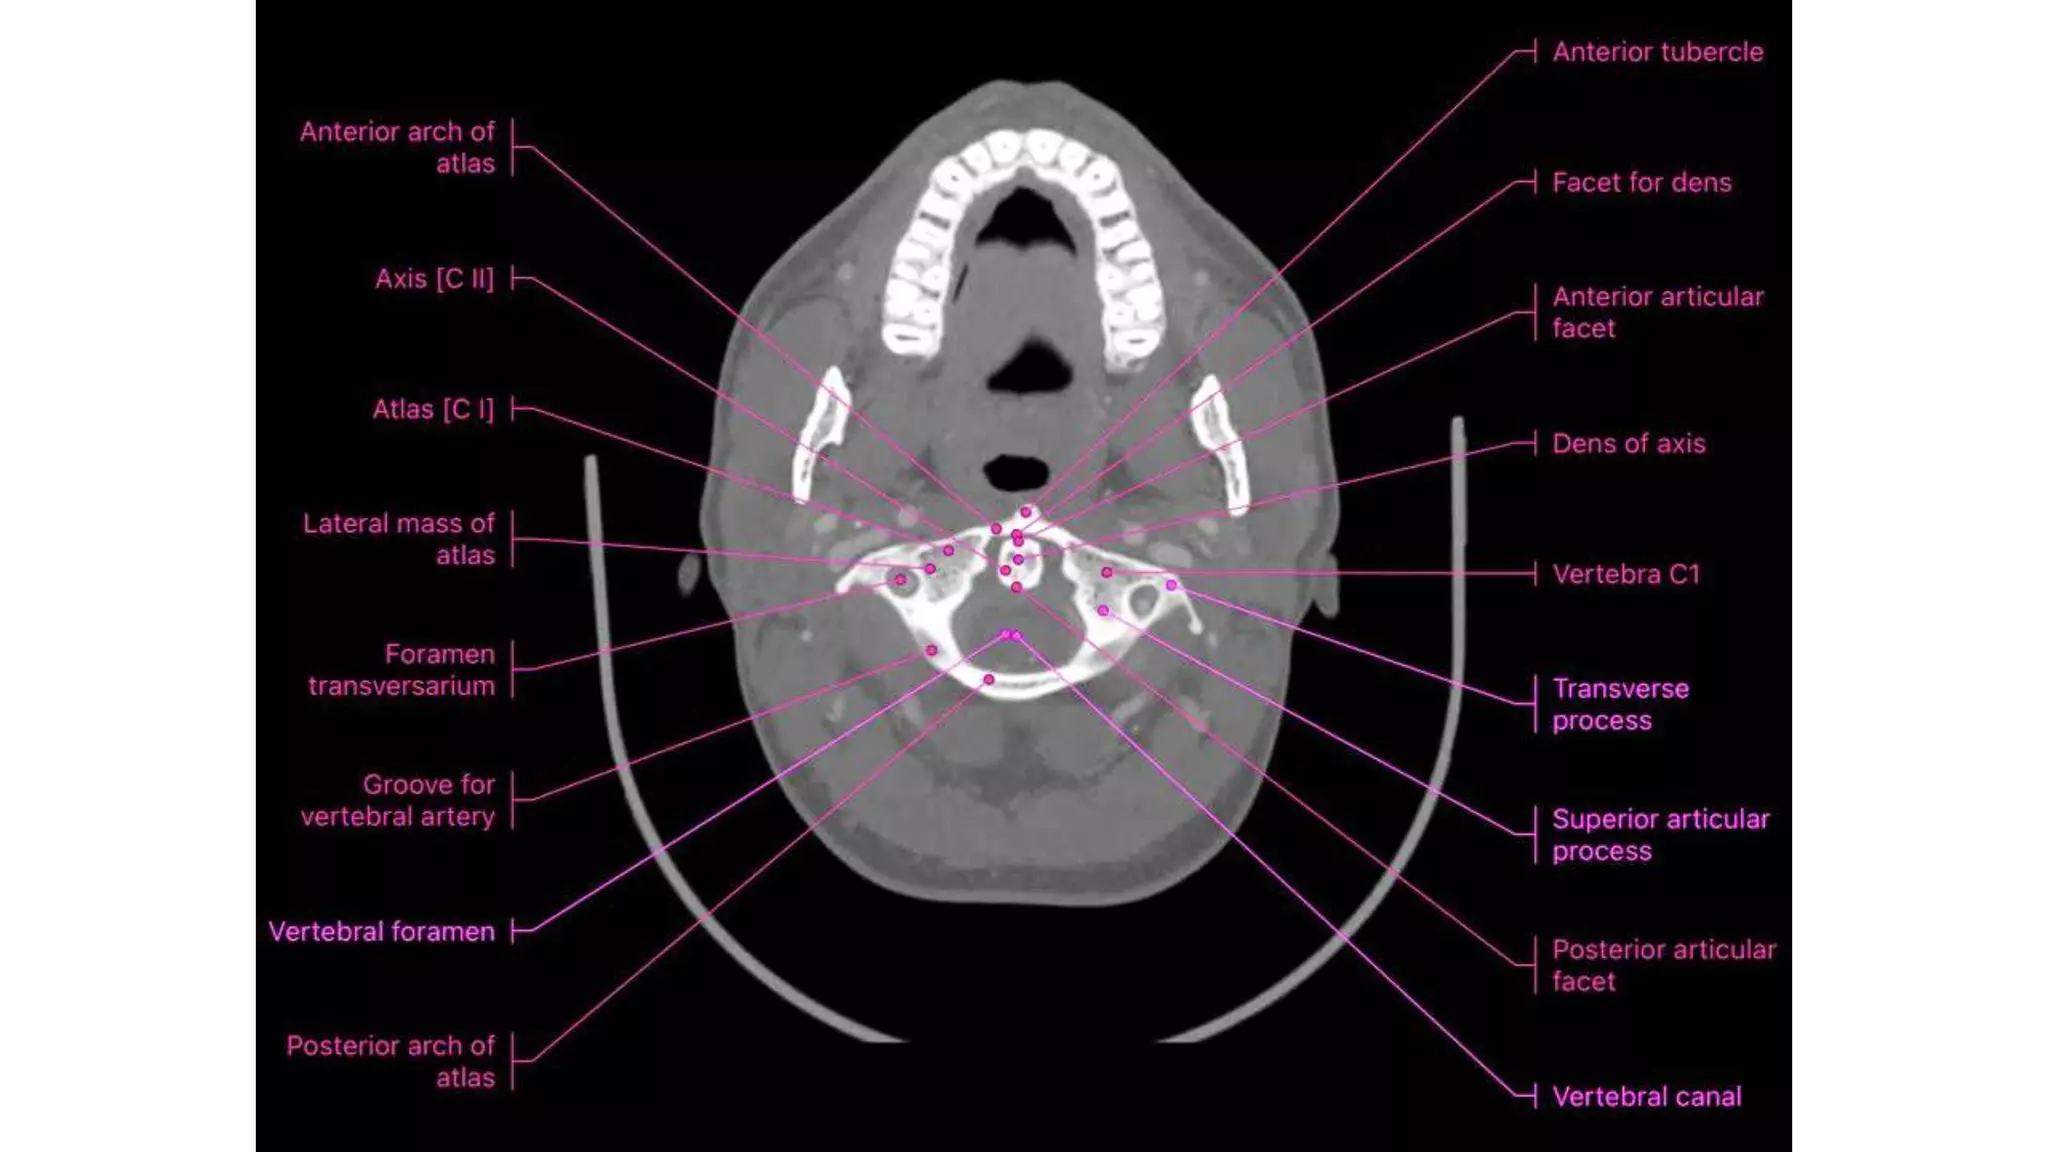

This three-dimensional reconstruction from computed tomography (CT) axial images focuses on the occipital–

cervical junction and the C1-2 (atlantoaxial) junction

The skull base has been cut away nearly completely in this

CT model, allowing the ring of C1 and its relationship to the

dens of C2 to be seen in detail.

C1 and C2 view of the normal cervical spine

This three-dimensional reconstructionfrom computed tomography (CT) axial images focuses on the occipital– cervical junction and the C1-2 (atlantoaxial) junction

• 13.

The skull basehas been cut away nearly completely in this CT model, allowing the ring of C1 and its relationship to the dens of C2 to be seen in detail. C1 and C2 view of the normal cervical spine